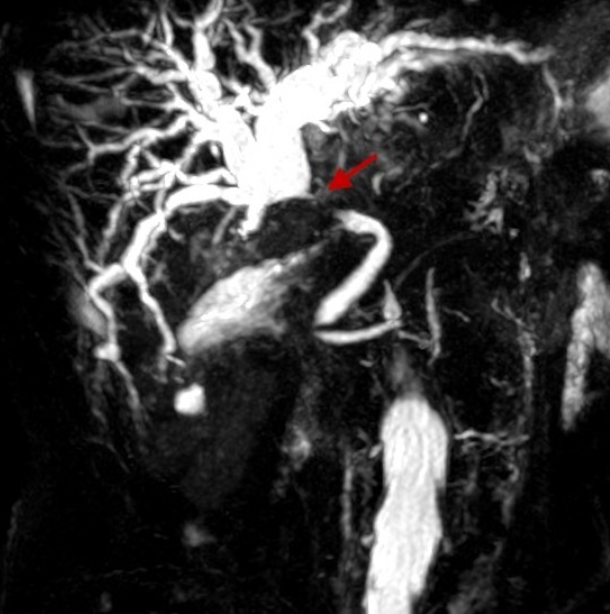

- KLATSKIN TUMOUR (image)

What is this?

Two types?

- Cholangiocarcinoma

- adenocarcinoma of the biliary tree

- Two types

- scirrhous type

- worse prognosis

- Polypoid type

- scirrhous type